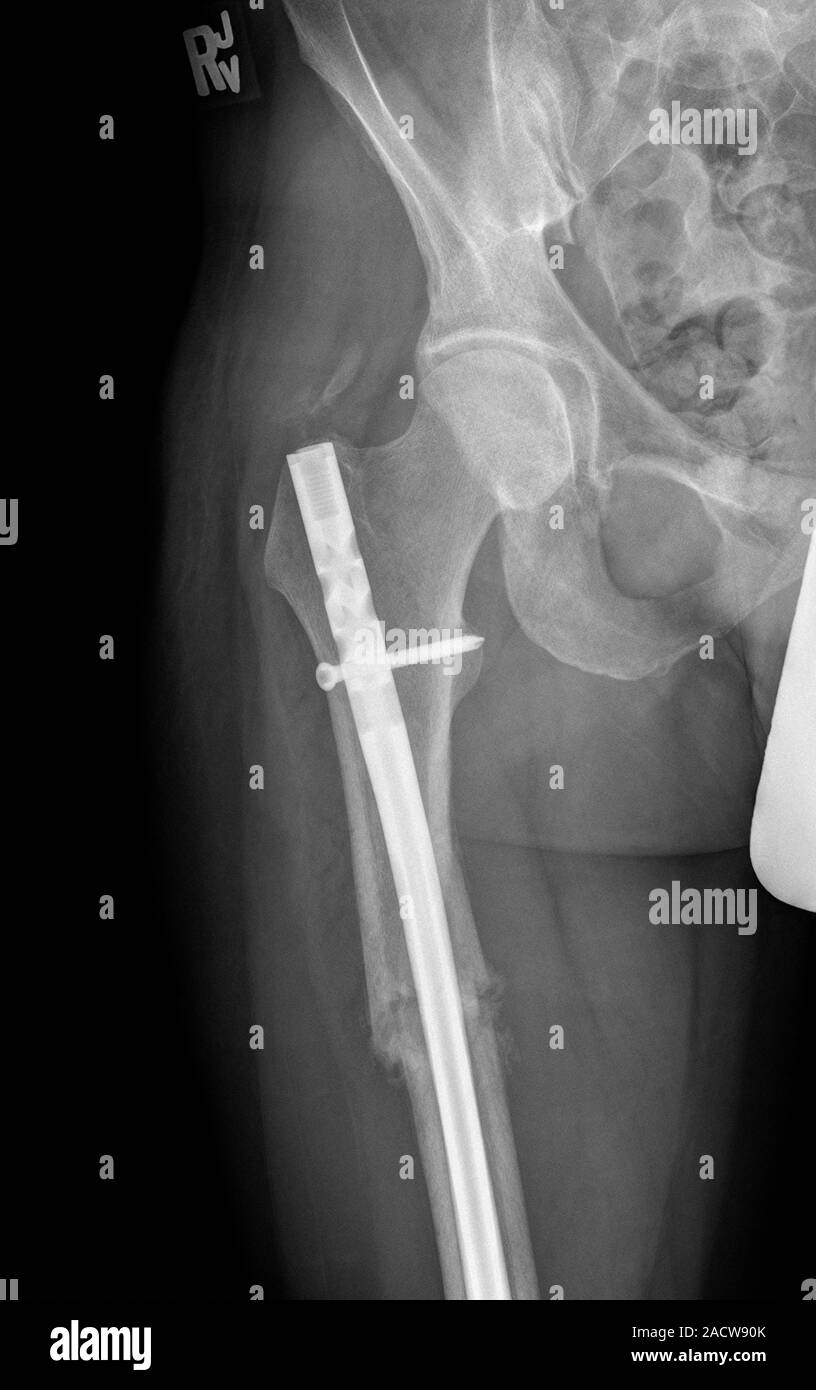

DIstal femur fracture before and after surgery. IMHS rod with screws.

DIstal femur fracture before and after surgery. IMHS rod with screws. Problems With Titanium Rod In Femur  The results of this review support the use of titanium implants in certain clinical fracture scenarios. Intramedullary (im) rods are used to align and stabilize fractures. Titanium femurs are real, but so are their risks. Im rods are inserted into the bone marrow canal in the center of the long bones of the extremities. In clinical studies of fracture fixation.. Problems With Titanium Rod In Femur.

Pinned femur fracture. Xray of a titanium metal rod and screw (white Problems With Titanium Rod In Femur  People who have implants also may report pain and irritation at the site where the implants were placed. Many fractures could have been avoided. Screws, rods, or other implants used during orthopedic surgery can cause infection. Titanium femurs are real, but so are their risks. Recovery was difficult and the best bend i ever attained was 102. The results of. Problems With Titanium Rod In Femur.